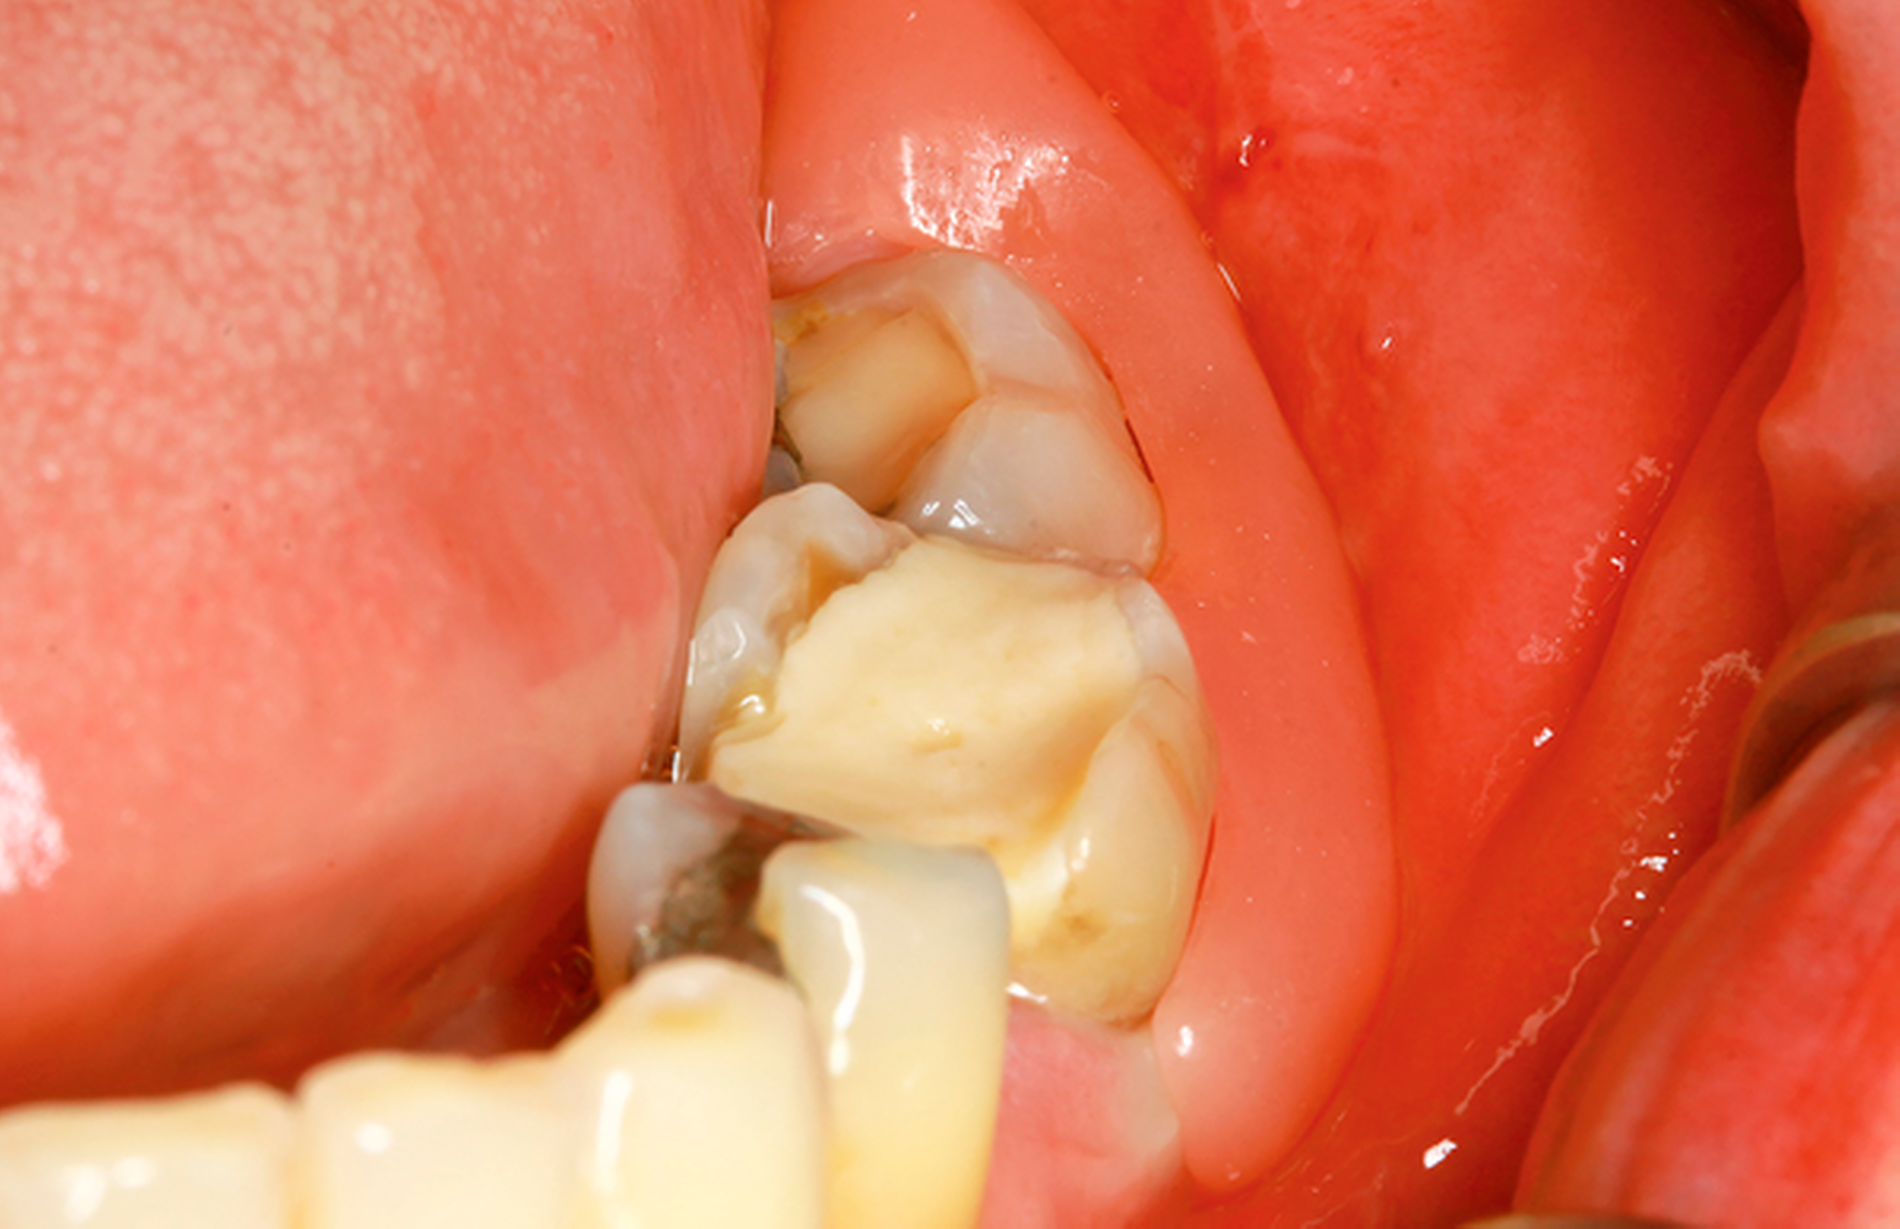

Eine 72-jährige Patientin wurde zur Therapie einer Zyste in regio 48 in unser MVZ überwiesen. Es handelte sich um einen Zufallsbefund im OPTG. Klinische Beschwerden wurden von der Patientin verneint (Abbildung 2a). Vorerkrankungen bestanden abgesehen von Migräne nicht. Zur Beurteilung der Zystenausdehnung erfolgte eine Computertomografie des Gesichtsschädels, die insbesondere eine basal stark ausgedünnte Kortikalis zeigte. Nach Erörterung der therapeutischen Möglichkeiten entschied sich die Patientin für eine Zystostomie, da die Zystektomie mit einem erheblichen Frakturrisiko, der möglichen Schädigung des N. alveolaris inferior sowie einer Behandlung in Allgemeinanästhesie verbunden gewesen wäre. In Lokalanästhesie wurde über einen marginalen Zugang in regio 47-48 eine Biopsie des Zystenbalgs gewonnen sowie eine Drainage ins Zystenlumen inseriert. Histologisch konnte eine follikuläre Zyste gesichert werden.

Die täglichen Spülungen des Lumens über die einliegende Drainage mit NaCl-Lösung erfolgten durch die Patientin selbst nach entsprechender Instruktion. Dies führte sie für sechs Monate selbstständig durch. Zwischenzeitlich musste das Drainageröhrchen wegen Verlusts erneut inseriert werden. Im DVT zeigte sich nach sechs Monaten eine signifikante Ossifikation am Rande des Zystenlumens und der N. alveolaris inferior wies wieder eine knöcherne Ummantelung auf (Abbildung 2b). Somit konnten die Zystektomie des verbliebenen Befunds und die Entfernung von 48 in ITN erfolgen. Dabei und postoperativ traten keine Komplikationen auf. Zahn 47 ist unverändert vital. Die extrem verlagerten Zähne 18 und 28 wurden auf Wunsch der Patientin belassen. Nach vier Monaten stellt sich im OPTG ein nahezu vollständig ossifizierter Defekt dar und die Patientin ist vollkommen beschwerdefrei (Abbildung 2c).